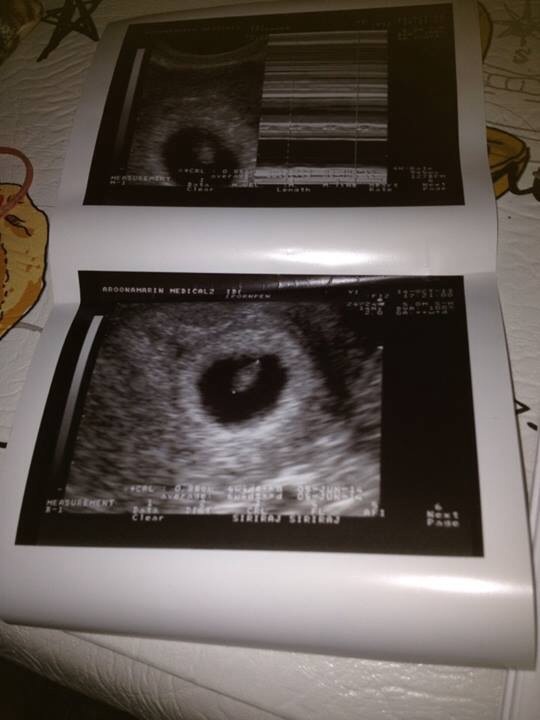

หมอบอกไม่ใช่8สับดาห์ แต่แค่6สับดาห์ เป็นได้2กรณี แจ้งประจำเดือนผิด และอื่นๆ

ตกไข่ไม่ตรง หมอนัดอีก2อาทิตย์ซาวด์ช่องคลอดอีก แจ้งว่าถ้าเด็กไม่มีการเจริญเติบโต

ก็ต้องมาคุยกัน ทั้งที่หมอก็แจ้งว่าเด็กหัวใจเต้นปรกติ ถุงน้ำคร่ำสวย (ลืมเดือนกุมภาเราก็35

และเคยแท้งเมื่อ3ปีกว่าและก็รอมานาน เป็นเพราะแบบนี้มั้งหมอเลยซาวด์ถี่

เมื่อวันที่14/10/56หมอนัดซาวแต่ซาวช่องคลอด